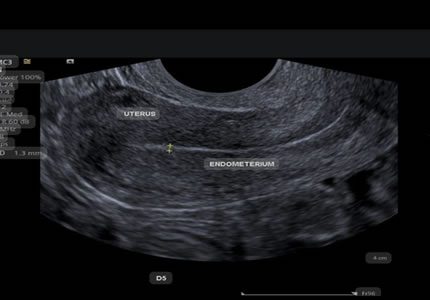

Comprehensive pelvic ultrasound evaluations for a wide range of non-pregnancy female health concerns, symptoms, or referrals.

Routine & Diagnostic Gynaecological Scans

Symptom-Based & Condition-Specific Scans